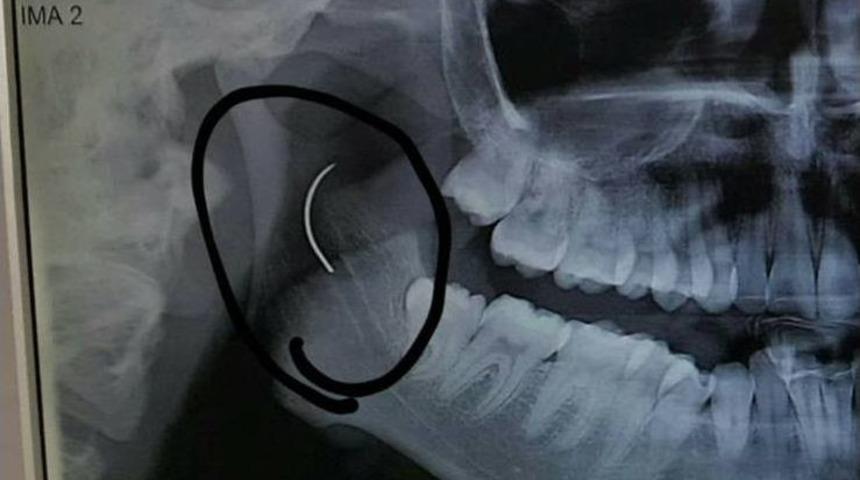

Manisa’nın Soma ilçesinde 3 yaşındayken olduğu bademcik ameliyatında boğazında ameliyat iğnesi unutulan 21 yaşındaki Meltem Cansız, o iğneden tam 18 yıl sonra geçirdiği başarılı bir operasyonla kurtuldu.Soma Devlet Hastanesi’nde bademcik şikayetiyle 1999 yılında ameliyat olan Meltem Cansız’ın boğazında iğne unutuldu. 18 yıl boyunca boğazında iğne ile yaşayan ve şu anda 21 yaşında olan Meltem Cansız’ın tüm hayatı acı ve ağrılarla geçti. Boğazındaki iğnenin acıları günden güne yıldan yıla artan Meltem Cansız, 11 yıl sonra 14 yaşında iğnenin fark edilmesiyle Ege Üniversitesi’nde bıçak altına yattı ancak ameliyatı başarısız geçti. Lise öğreniminden sonra sağlık sorunları nedeniyle üniversiteye hazırlanamayan Meltem Cansız, acılarına rağmen yılmadı sabırla bekledi ve geçirdiği başarılı ameliyatla o iğneden 18 yıl sonra kurtuldu.Boğazındaki iğneyle geçen 18 yılını anlatan Meltem Cansız, "3 yaşında geçirdiğim bademcik ameliyatında iğne boğazımda unutulmuş. Daha sonra iğneden dolayı 11 yıl sonra 14 yaşındayken kulak rahatsızlığım ortaya çıktı. Kafamın sağ tarafı ağrımaya başladı. Doktora gittik, hiçbir şey olmadığını söylediler. Sonrasında beni MR çekilmek üzere Akhisar’a yönlendirdi. Gecenin bir vakti MR’a girdim. Ancak bir türlü çekemediler. Benim üzerimde toka vs. metal bir şey olduğunu söylediler baktılar ancak bir şey yoktu. Üç yada dört defa MR’a girdim. Ancak bir türlü çekemediler. Sonra doktorumuz röntgene yönlendirdi. Röntgen görüntüsünde ameliyattan kalma bir çengelli iğnenin boğazımda olduğu görüldü. Bunun için beni Ege Üniversitesi’ne sevk ettiler. Burada doktorlar bu ameliyatı yapabileceklerini ancak riskinin çok olduğunu söylediler. Biz yine de kabul ettik. 1,5 saatlik operasyon geçirdim ancak iğneyi bulmadıklarını söylediler. 2 sene kadar araştırma yaptık. Birçok hastaneyle görüştük. Ancak ayağımda bir rahatsızlık meydana geldi. Ayağım için Ege Üniversitesi’ne gittik. Tekrardan beni ameliyat eden doktorumla görüştüm. ’Seni ben ameliyat ettim, tekrardan buna kalkışamam’ dedi. MR’a da giremezsin dediler. ’Sen bununla yaşamayı öğren’ en azından bunun için çabalama alınmaması daha iyi dediler. Ben daha genç bir kızım sonuçla bu iğneyle ömür boyu yaşayamazdım. Yaşanan bu olumsuzların ardından araştırmalarımız neticesinde en son İzmir’de özel bir hastaneye gittik. Oradaki doktorum Çağlar Çallı bey bana umut verdi. ’Bu iğneyi alacağız’ dedi. İnancımı kaybetmedim, sonucun ne olacağını bilmeden girdim ben o ameliyata. Ölüm, felç olma riskim çok fazlaydı. ’Yaşayamayabilirsin’ dediler, biz bile bile lades dedik. Sonucu da güzel oldu" dedi.14 yıl sonra iğne unutulduğu ortaya çıktıBaba Ahmet Cansız ise kızını 1999 yılında 3 yaşındayken bademcik sorunu nedeniyle Soma Devlet Hastanesi’ne götürdüğünü belirterek, "Bademcikleri nedeniyle çok sık hasta oluyordu. O günkü SSK’da doktorumuz ameliyat olması gerektiğini söyledi. Neticede ameliyat olduk. Ameliyat sonrasında aradan geçen süreçte kızım 17 yaşında geldiğinde yüzünde, sağ tarafında bir ağrının olduğunu, başının, kulağının ağrıdığını söyleyince kulak burun boğaz doktoruna gittik. İlaçlar verdi geçmedi, sonra bir daha gittik. Eklem arası bir iltihap olabilir diyerek MR istedi. Akhisar ilçesine MR çekilmeye gittik. Fakat bir türlü çekemediler. Daha sonra bir film çekildi ve iğne ortaya çıktı" diye konuştu."’İğne şah damarına yakın, kızın ölebilir’ dediler"Ege Üniversitesi’ne gittiklerini belirten baba Cansız, iğnenin şah damarına çok yakın olduğunun söylendiğini belirterek şunları söyledi: "Doktorlar çok tehlikeli bir ameliyat olacağını yanlış ya da en ufak bir hatada kızımızın bir tarafının felç kalabileceğini veya hayatını kaybedebileceğini söylediler. Biz bu riski göze alarak ameliyata müsaade ettik. Fakat iğneyi görüldüğü yerde bulamadıklarını söyleyerek alamadılar. Sonra İzmir Çiğli’de özel bir hastanede denedik. Kendisine binlerce kez teşekkür. Allah razı olsun. Çocuğumun boğazındaki iğneyi aldı. Dünyalar bizim oldu."